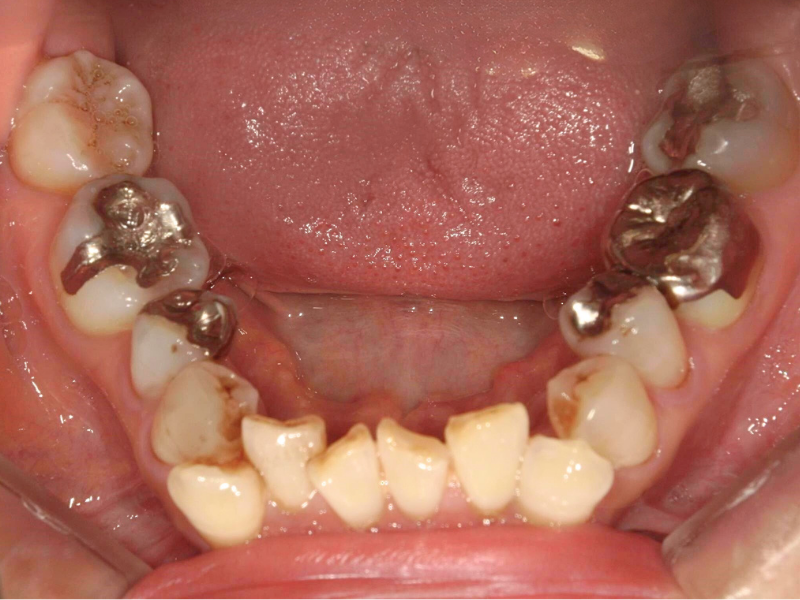

20代、男性、ワイヤー

| 施術内容 | 主訴:でこぼこで食べ物がよく挟まる。虫歯や歯肉炎に悩まされてきた。 詳細:ワイヤー矯正での歯並び改善 とても磨きやすくなったと満足されてます。 |

|---|---|

| 治療期間 | 16ヶ月(2/3現在 治療終了) |

| リスク・副作用 | ■リスク・副作用 ・治療の初期段階では、痛みや不快感が生じやすくなりますが、一週間前後で慣れます。 ・歯の動き方には個人差があるため、予想された治療期間より延長する場合があります。 |

| 費用 | ワイヤー矯正 60万円(税込660,000円) |